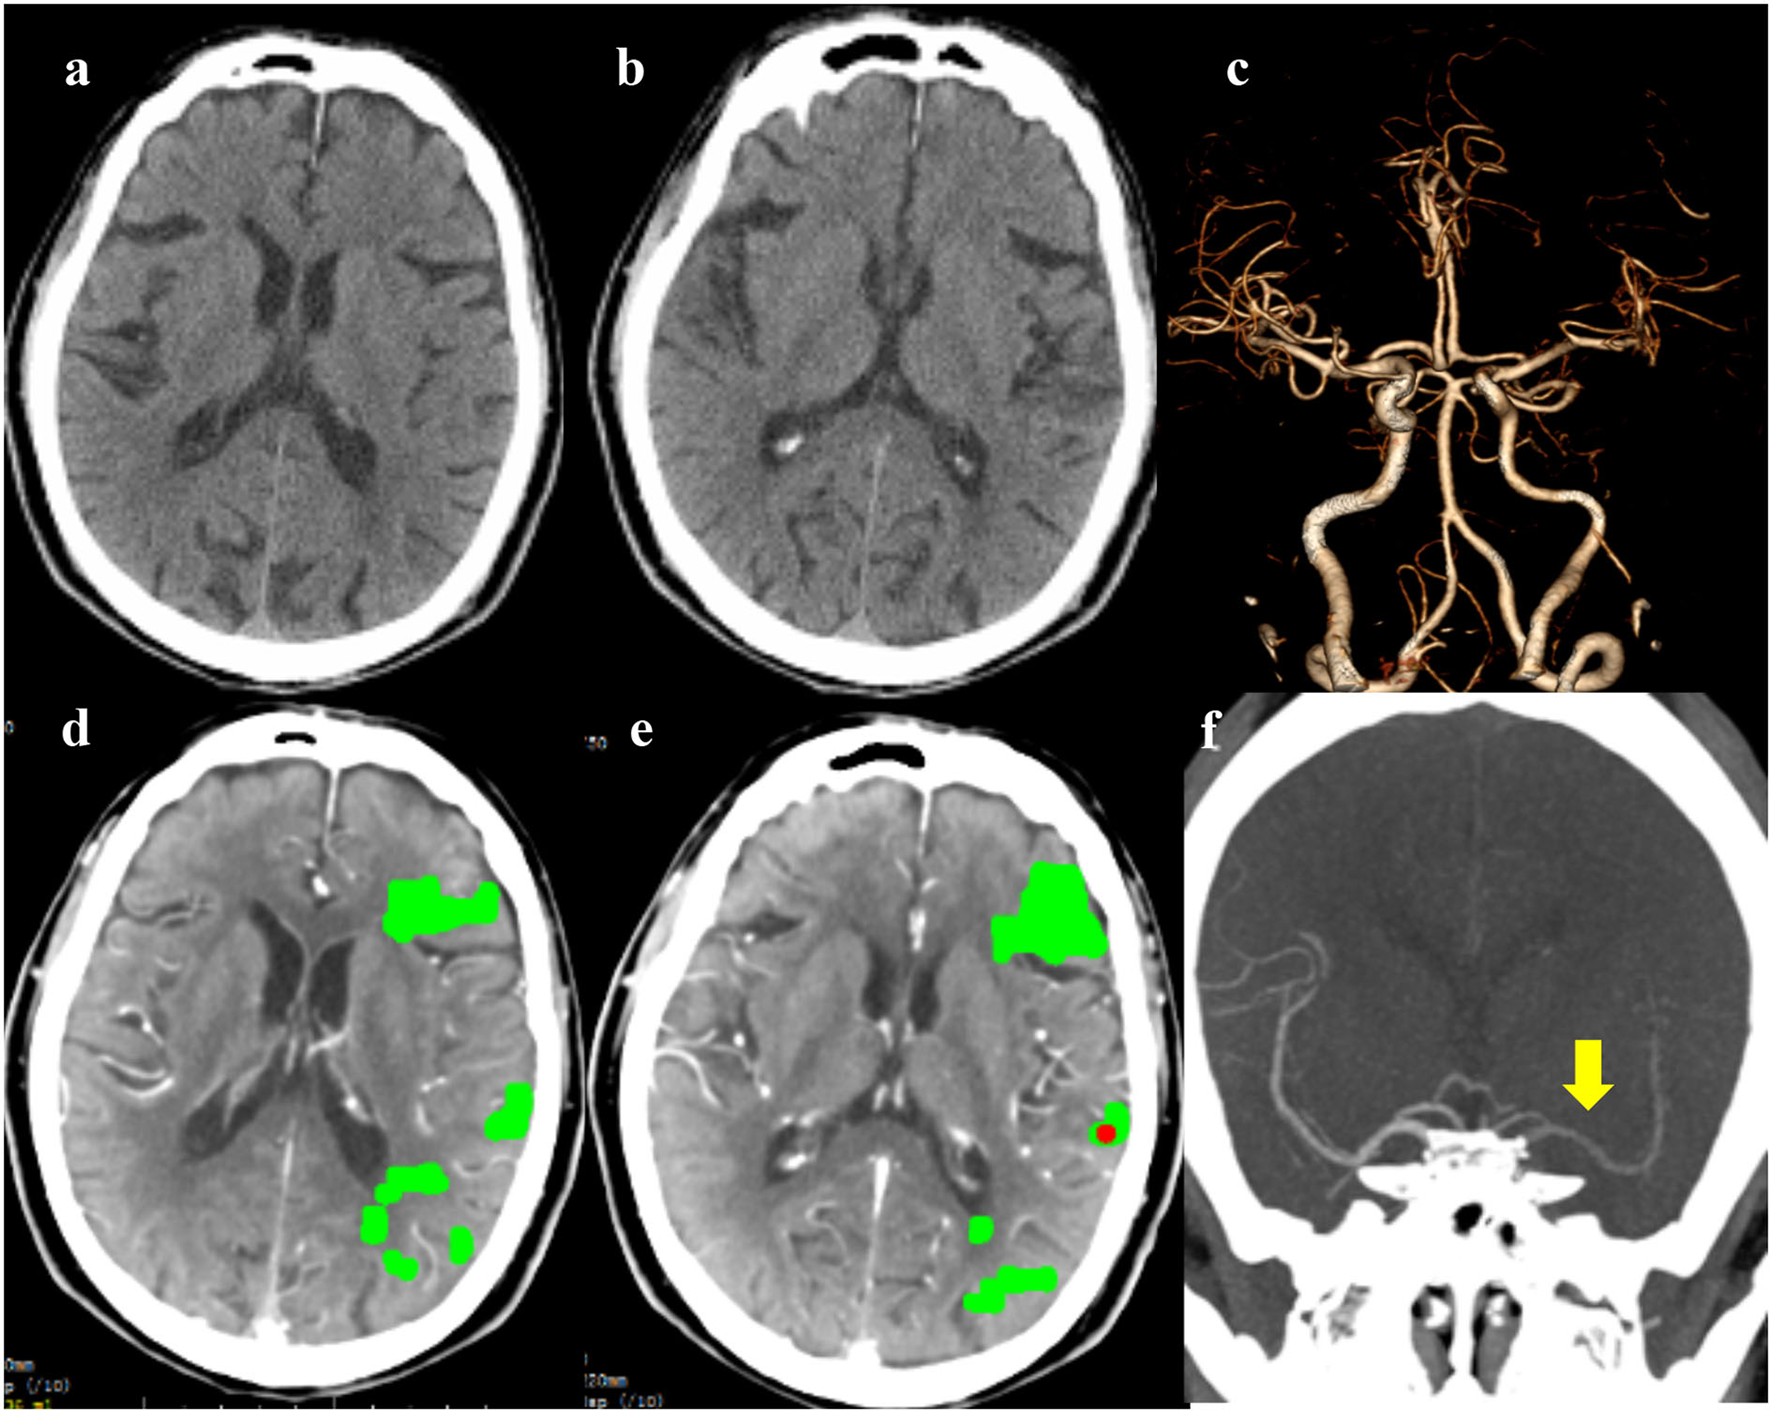

Figure 1

The emergency non-contrast CT (NCCT) (a,b) and cranial CT angiography (CTA) (c) did not show obvious cranial abnormalities; whole-brain CT perfusion (WB-CTP) indicated the left hemisphere core infarction (d,e); The 4D-CTA reconstruction showed delayed imaging of the left middle cerebral artery [(f), yellow arrow].